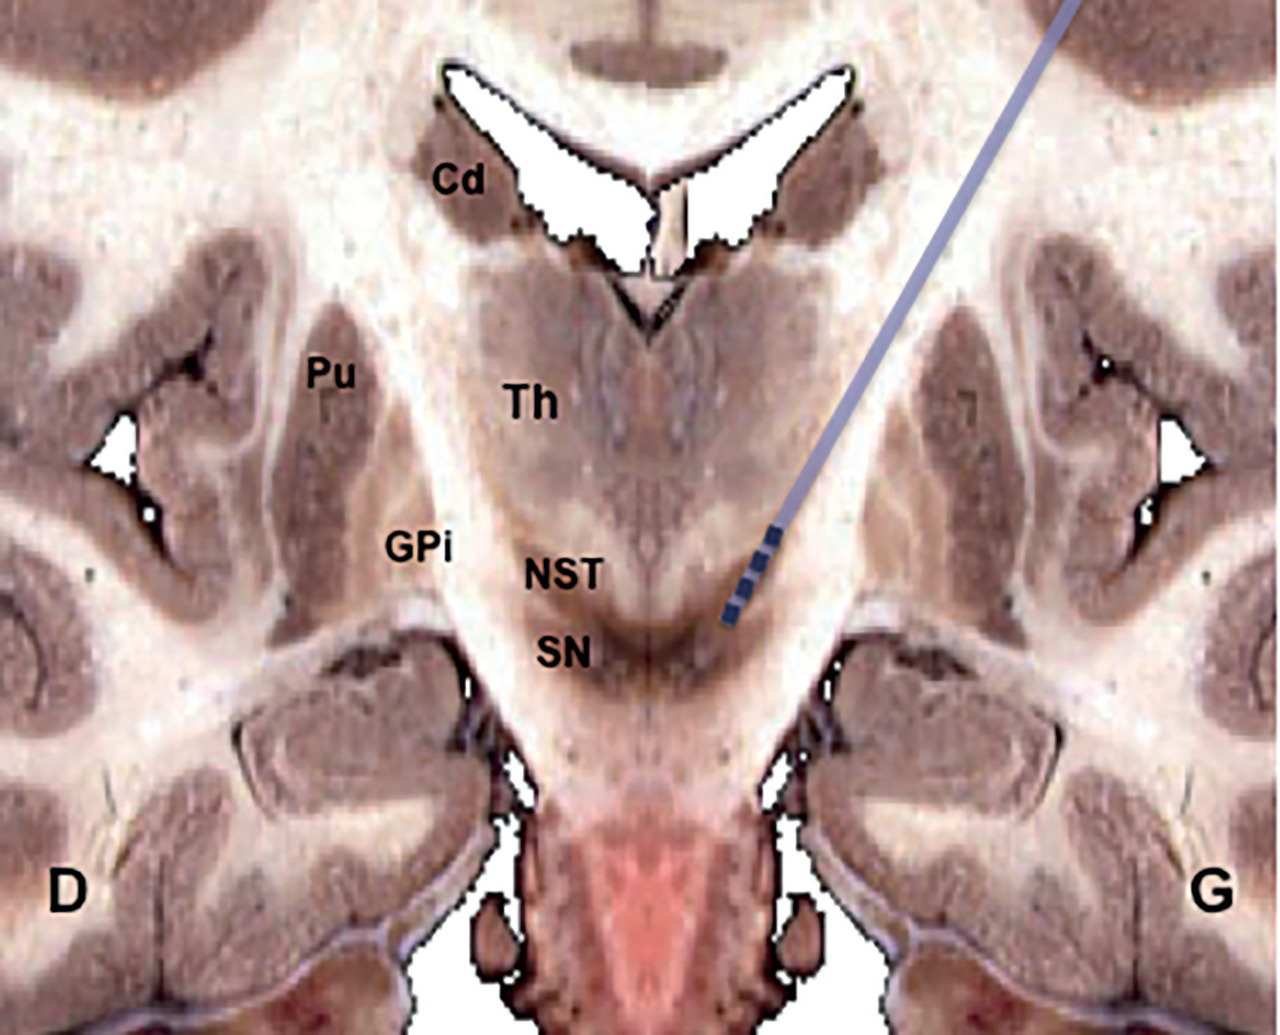

Des études expérimentales chez l’animal ont démontré qu’il était possible « d’exclure » le pallidum interne et certaines zones thalamiques par inhibition électrique à haute fréquence. Dans cette région, selon des essais chez les primates,3 le noyau sous-thalamique (NST) avait déjà paru une cible intéressante pour lutter contre les symptômes moteurs. Cependant, sa lésion définitive provoquant des effets secondaires impressionnants (hémiballisme), il avait été mis de côté. Son retour dans les cibles neurochirurgicales s’est fait grâce à la modulation neuronale réversible (figure), dont l’innocuité a été démontrée lors de protocoles de stimulation thalamique contre les tremblements.2

La méthode appliquée à la MP comporte l’implantation de deux électrodes profondes, une par hémisphère, reliées à un stimulateur placé sous la peau du thorax (comme d’autres pacemakers) ou parfois du ventre. La stimulation qui module l’activité des circuits moteurs exige un réglage très fin chez chaque patient. Une dizaine de jours d’hospitalisation sont nécessaires pour programmer le matériel et ajuster les doses de L-dopa. La période d’adaptation et de suivi rapprochés dure de 3 à 6 mois.